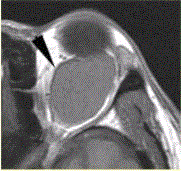

患者女,30岁,左眼球突出,运动障碍7个月。MRI平扫示左肌锥内等T信号影(下图)。增强扫描示均匀增强,眼肌、眼环正常。眼眶海绵状血管瘤MR表...

问题 患者女,30岁,左眼球突出,运动障碍7个月。MRI平扫示左肌锥内等T信号影(下图)。增强扫描示均匀增强,眼肌、眼环正常。 眼眶海绵状血管瘤MR表现是

选项 A.多位于肌锥外 B.为迂曲条状 C.T2加权像为低信号 D.T2加权像为高信号 E.病变信号不均匀 F.渐进性强化

答案 DF